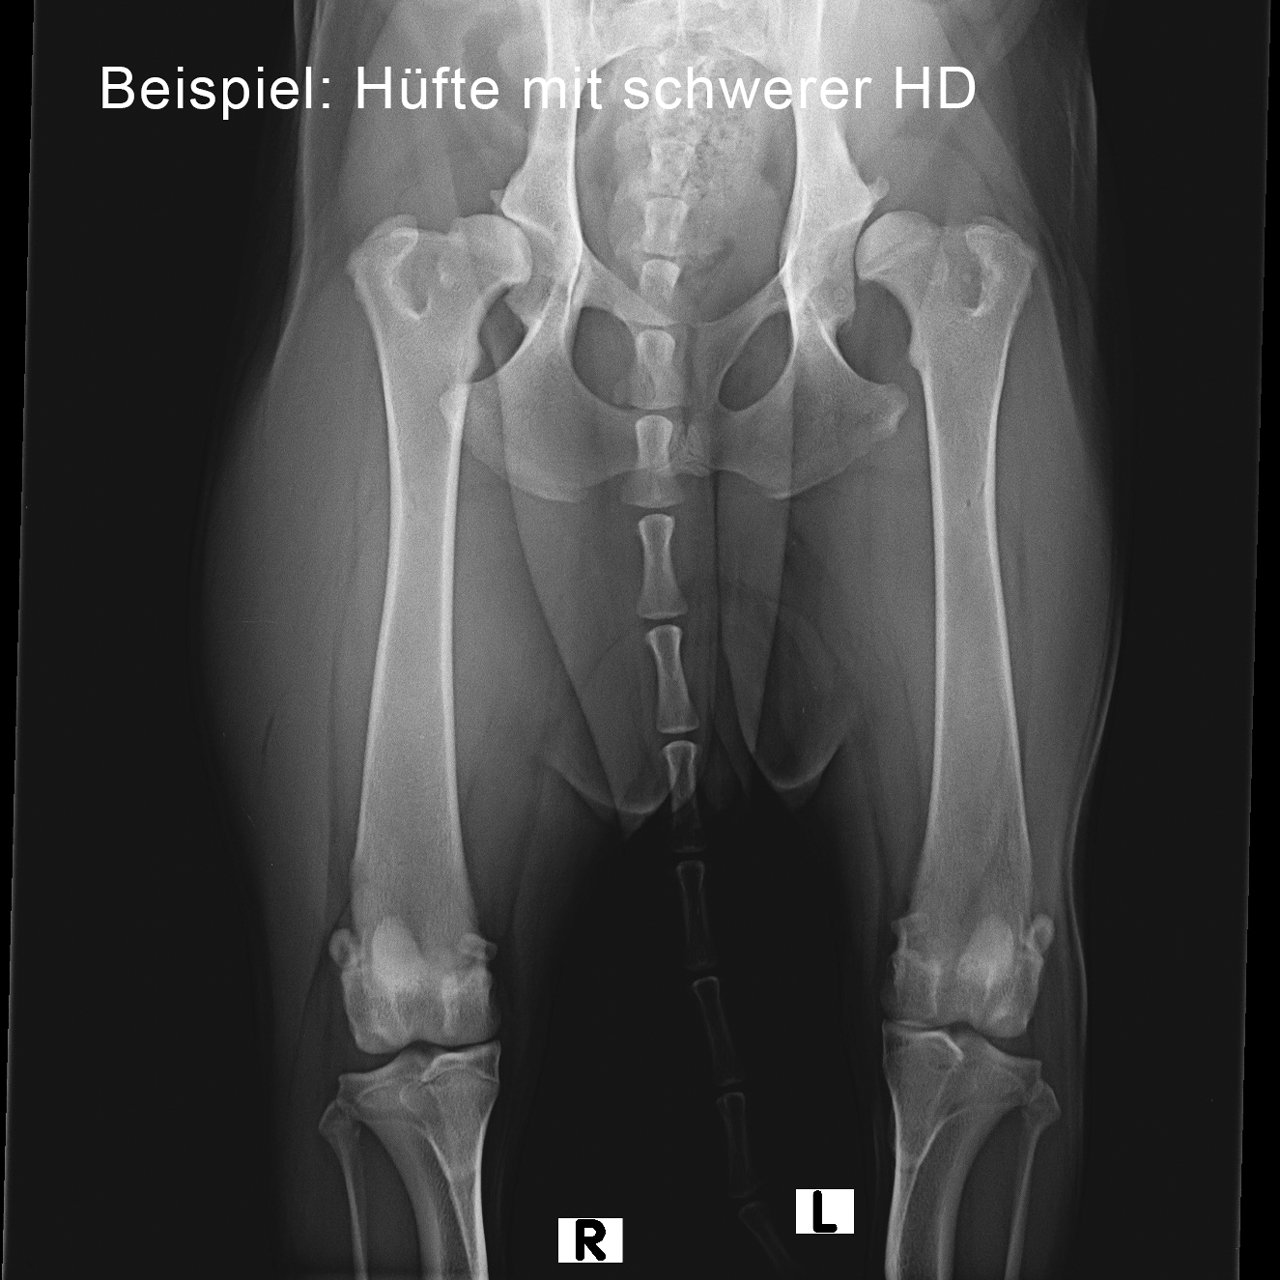

Graf Barf: Viele Züchter möchten für ihre Zuchtstatistik Röntgenaufnahmen des Welpen von Hüfte und Ellenbogen. Macht es generell Sinn, Junghunde röntgen zu lassen, um zu überprüfen, ob alles in Ordnung ist?

Dr. Susanne Wisniewski: Das stimmt, für die Ahnenstatistik und das Zuchtbuch der Züchter sollen alle Nachkommen überprüft werden, ob insbesondere Hüfte und Ellenbogen eine genetisch gesunde Disposition haben. Das ist gleichzeitig für die zukünftigen Welpenkäufer wieder ein sehr wichtiger Indikator. Dies geschieht dann, wenn der Hund ca. ein Jahr alt und ausgewachsen ist.

Hundebesitzern, die bereits schlechte Erfahrungen, z.B. mit schlechten Hüften oder Ellenbogen, gemacht haben – insbesondere bei großen Rassen mit Rassedispositionen –, kann man durchaus raten, ihren Welpen mit 5½ bis 6 Monaten einem orthopädisch geschulten Tierarzt vorzustellen. Der Tierarzt prüft das Gangbild und die Gebissstellung des Hundes und kann evtl. eine Röntgenaufnahme machen. Denn die Qualität der Hüfte kann jetzt bereits sehr gut beurteilt werden, und man kann unter Umständen im Ernstfall schon gezielt reagieren und helfen.